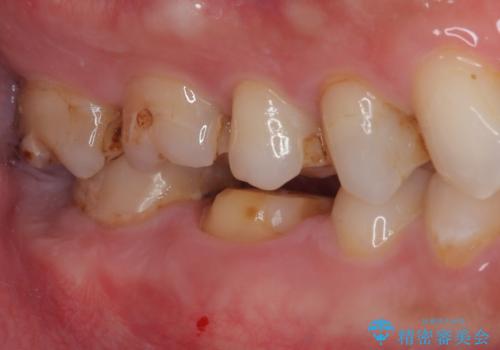

- セラミックの詰め物が欠けたのでやり替えたいとのことで来院された患者様です。

右下の6番目の歯は初診時から詰め物が大きかったため、被せものでの治療を提案していましたが、患者様の強いご希望でセラミックの詰め物(セラミックインレー)での治療をされていました。今回メインテナンス時に来院されたときに被せもの(オールセラミッククラウン)での治療を再度提案させていただき、患者様にも納得をしていただいたうえで、オールセラミッククラウンによる治療を行いました。

拡大鏡視野下で、セラミックの詰め物(セラミックインレー)、虫歯の除去を行い、オールセラミッククラウンに適した形に整えました。

歯と歯茎の間に圧排糸と言われる糸を入れてシリコーン印象材にて型どりをしました。